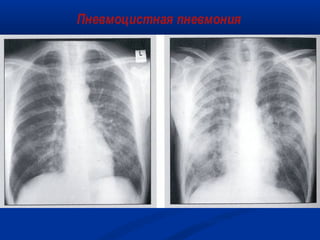

Пневмоцистная пневмония

Рентгенография грудной клетки:



признаки дыхательной недостаточности (с цианозом или без),

одышка

сухой кашель

при физикальном исследовании грудной клетки нарушения

минимальны или отсутствуют

облаковидное снижение прозрачности в нижних отделах обоих

легких

двусторонние очаговые тени

норма

Подтверждение диагноза:

обнаружение цист возбудителя в мокроте или жидкости,

полученной при бронхоальвеолярном лаваже

снижение функции внешнего дыхания

Из коллекции слайдов UCHSC AETC